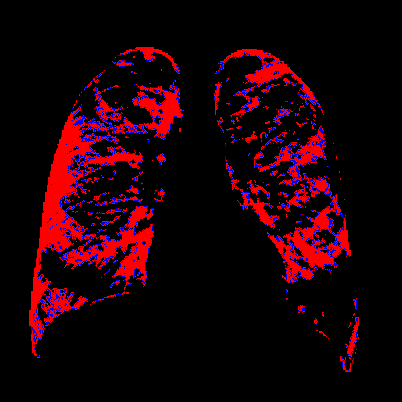

Side-by-side inspection of the generated healthy counterfactuals (as per fig. 2) suggests that, as required, only minimal perturbation is made to the original image with respect to healthy pixels -i.e. localized image sites without structural medical defects. (In the top row, the medical structural defect in the original image is due to a lung opacity, and characterized via a relatively complex interaction between the imaging modality and subject manifesting as ‘gaps’ in the corresponding portions of the lung scan). The healthy/non-healthy discrepancy maps in all of these cases are obtained via masked subtraction of the original image from the generated image (the ground truth segmentation masks correspond to the broad area of interest –i.e. the complete lung). The generated healthy tissue is thus a subset of the mask and is shown in the final column of fig. 2 for the respective cases.

In the context of a VANT-GAN[20]-based approach, this highlighted material constitutes the diagnostic counterfactual visual attribution, i.e. the selection of material relevant to the diagnosis of the unhealthy condition. Healthy counterfactual generation was performed for the complete datasets in the three unhealthy classes, i.e Lung opacity, Viral Pneumonia and COVID, examples of which are given in fig. 3 for the three classes (all of the generated healthy counterfactuals from this experiment can be found on https://huggingface.co/ammaradeel/diffusionVA). Visual inspection indicates that the generated counterfactuals are, in general, visually plausible with minimal perturbation made to the unhealthy image overall. Moreover, the healthy counterpart generation does not appear to unnecessarily affect aspects of the images unrelated to the medical condition, the model selectively making changes to the unhealthy regions in a structurally plausible manner, e.g. generating missing portions of the lung without generating extraneous lung material where it would be expected to normally exist (e.g. in the abdominal cavity).